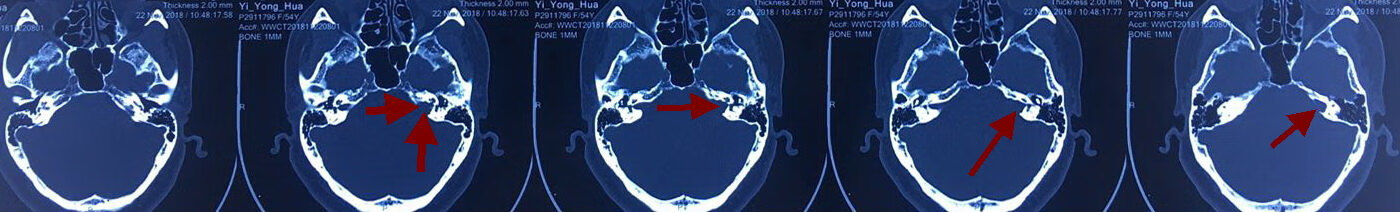

术前影像如下:

术前内听道CT显示左侧内听道口较对侧明显扩大,呈喇叭口状。